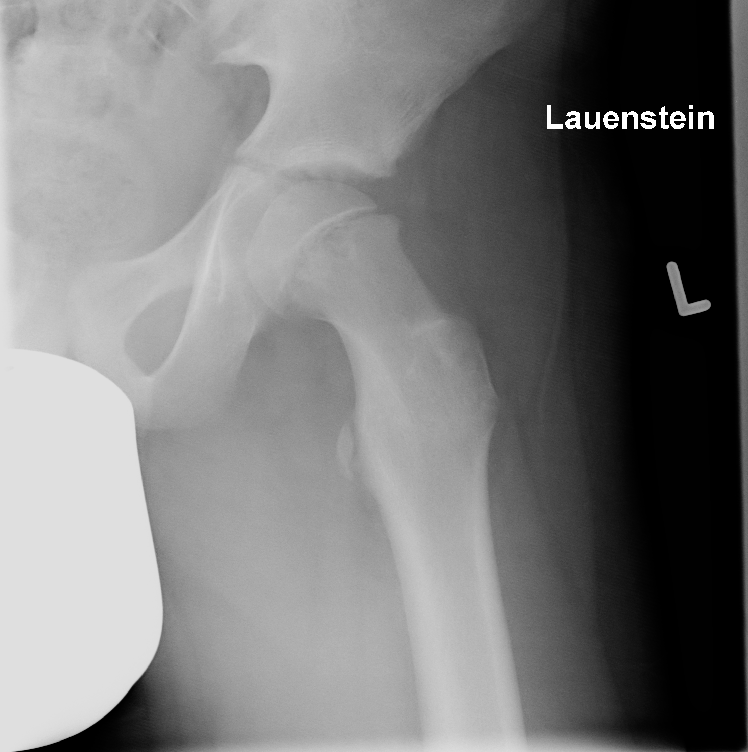

SCFE - longitudinal images over 6 years:...

Schleswig Holstein, Germany

Paediatric - PCCF